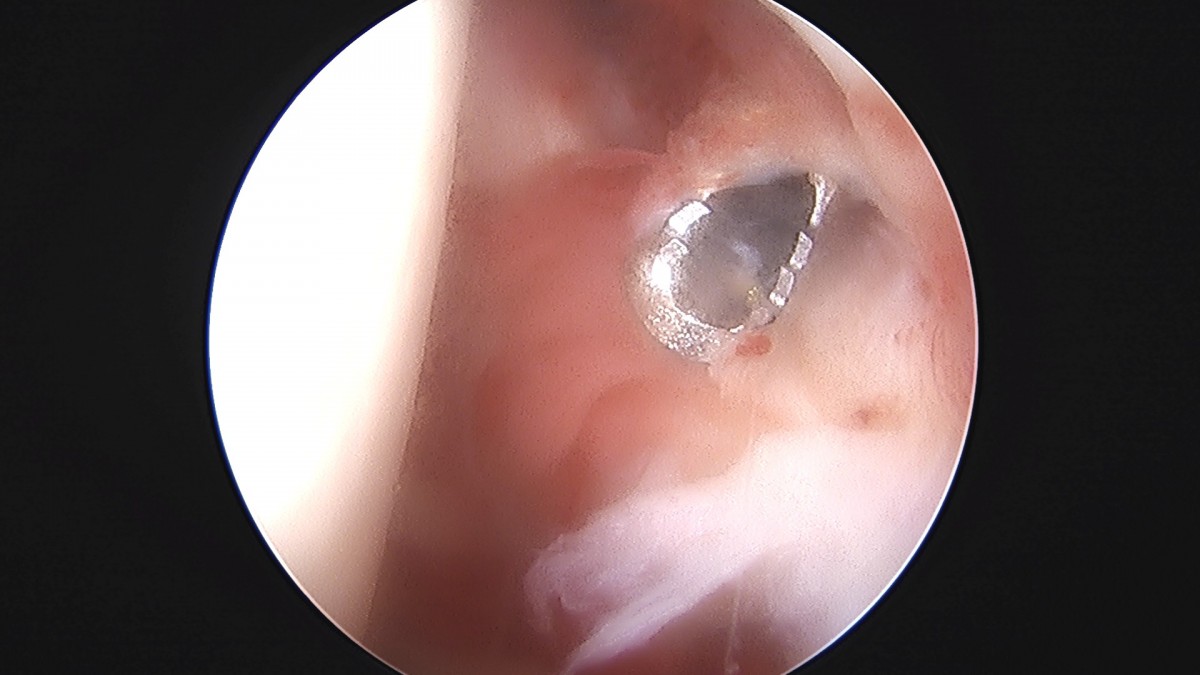

정지영원장님 어깨 관절낭 이완술 및 석회제거술 박설O 환자

작성자 최고관리자 댓글 0건 조회 732회 작성일 25-09-16 16:59